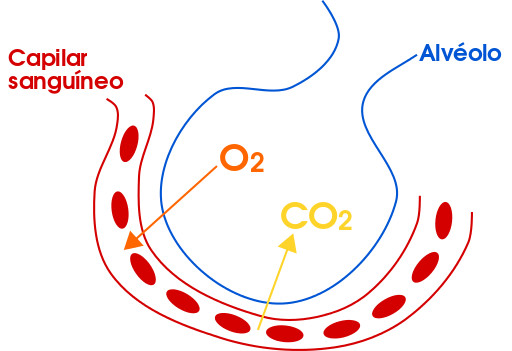

La trascendencia de los alvéolos, diminutos sacos de aire, se manifiesta en su papel crucial en el intercambio gaseoso. Estos pequeños compartimentos, rodeados por una red de capilares sanguíneos, facilitan la difusión del oxígeno desde el aire hacia la sangre y, simultáneamente, permiten que el dióxido de carbono sea expulsado de la sangre hacia el aire exhalado.

Intercambio de gases (respiración) en los alvéolos: La función principal del sistema respiratorio es facilitar el intercambio gaseoso. Este proceso culmina en los alvéolos, pequeños sacos de aire ubicados en los pulmones. Aquí, el oxígeno se difunde desde el aire hacia la sangre a través de las delgadas membranas alveolares, mientras que el dióxido de carbono se desplaza en dirección opuesta. Este intercambio es esencial para el suministro continuo de oxígeno a los tejidos y la eliminación de los desechos metabólicos.